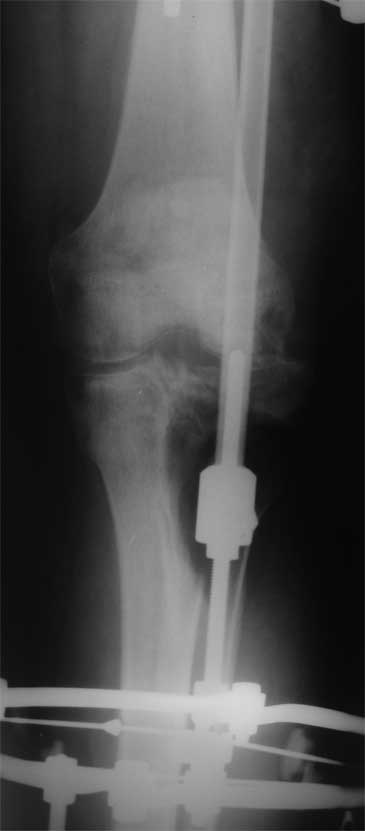

2. Хотелось бы увидеть снимки раннего периода, лучше после травмы, а также КТ. Интересует целостность плато б/б кости. По представленным

снимкам возникает подозрение, что наружный мыщелок отделен. Или это так кажется?

> Хотелось бы увидеть снимки раннего периода, лучше после травмы, а также КТ. Интересует целостность плато б/б кости. По представленным

- нет, скорее всего не кажется, вероятно он отделен, но, скорее всего живой и неподвижный (иначе рассосался бы)

У пациента жестокая эквинусная контрактура голеностопного сустава и почти наверняка - разгибательная в коленном суставе.

Не поврежден ли малоберцовый нерв?